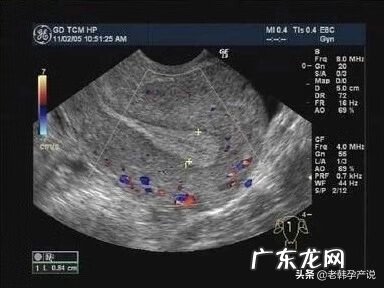

文章插图

上图是优势卵泡直径达到18mm时子宫内膜的图像,呈明显三线征,中间的宫腔线回声强,上面的一条线以及下面一条线与宫腔线之间的组织呈低回声 。